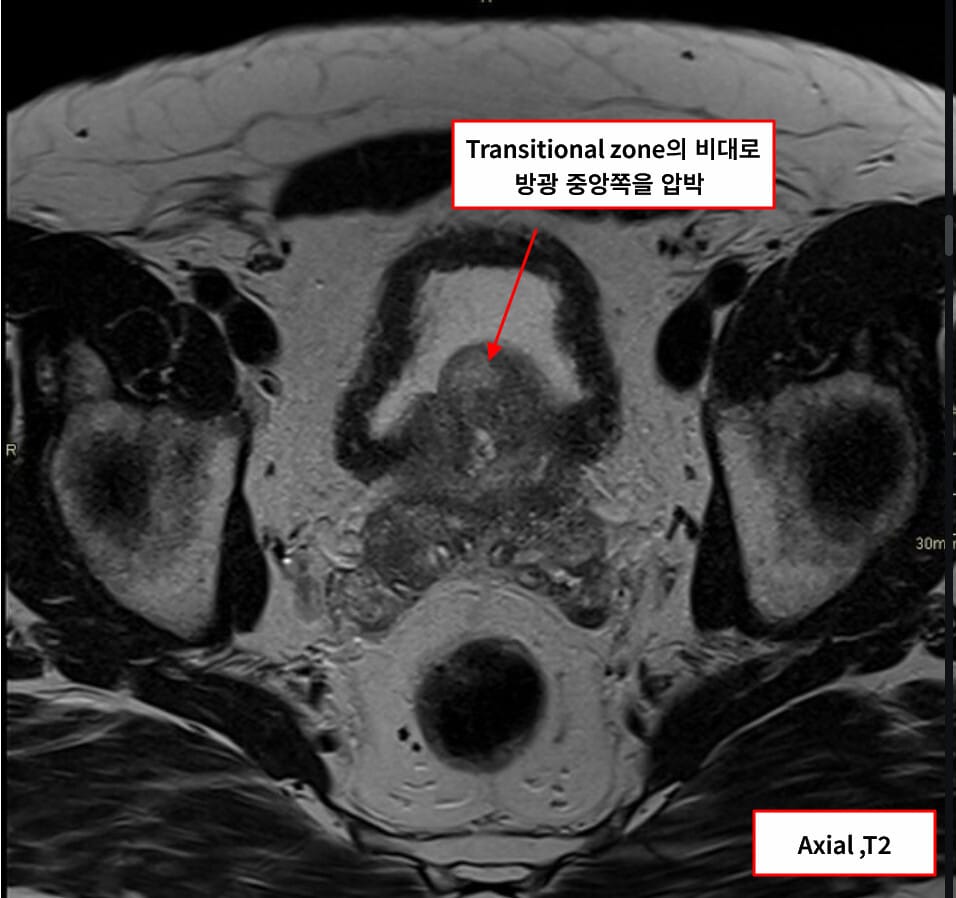

영상소견 정리

초음파 및 MRI에서 전립선 용적 증가와 중간엽(transition zone) 비대가 특징적입니다.

| 🔍 특징적 영상소견 요약 |

| ✅ 전립선 용적 증가 (≥30 mL) |

| ✅ 중심부 압박 및 요도 협착 |

| 중앙 요도를 압박하며 narrowing 보임 |

| ✅ 방광 잔뇨량 증가 |

| 비대에 의한 배출 장애로 잔뇨 발생 |

Bickle I, Benign prostatic hyperplasia. Case study, Radiopaedia.org (Accessed on 17 May 2025) https://doi.org/10.53347/rID-206343